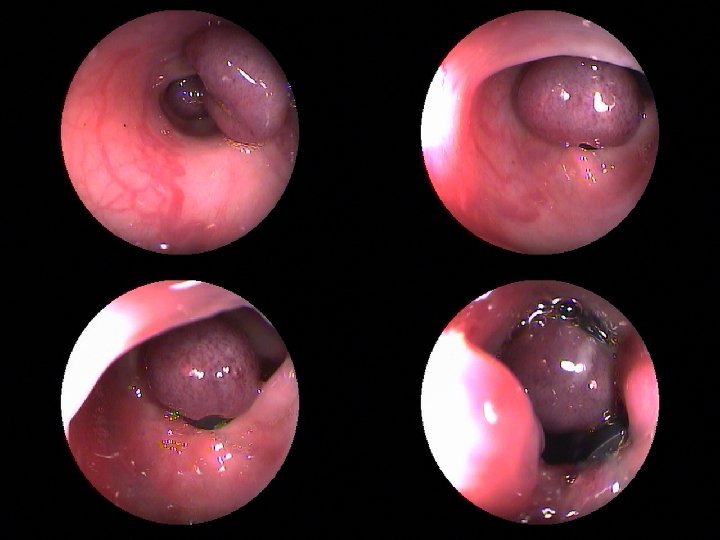

Осложнения • Рецидив кровотечения (8, 2%) • Ощущение инородного тела в пищеводе - (78%) • Субфебрильная температура - (82%)

Результаты эндоскопического лигирования • Рецидив кровотечения – 8, 2% • Летальные исходы – 6, 6% • Среднее количество сеансов – 1 -2

Отдаленные результаты (48 месяцев) • Повторные кровотечения – 19, 67% • Летальные исходы – 16, 39% • Среднее количество повторных сеансов – 1 -2 • Рецидив венообразования (48 мес) - 86%

Классификация ВРВП K. -J. Paquet (1983 г. ) • 1 -степень: продольные незначительно возвышающие над слизистой оболочкой, одиночные узлы диаметром до 0, 4 см; • 2 -степень: извитые, более расширенные выступающие менее чем на 13 от просвета пищевода, диаметром до 0, 8 см; • 3 -степень: выступающие более чем на 13 от просвета пищевода, имеют псевдоопухолевый вид, диаметром более 1 см. • 4 -степень: полностью прикрывающие просвет пищевода